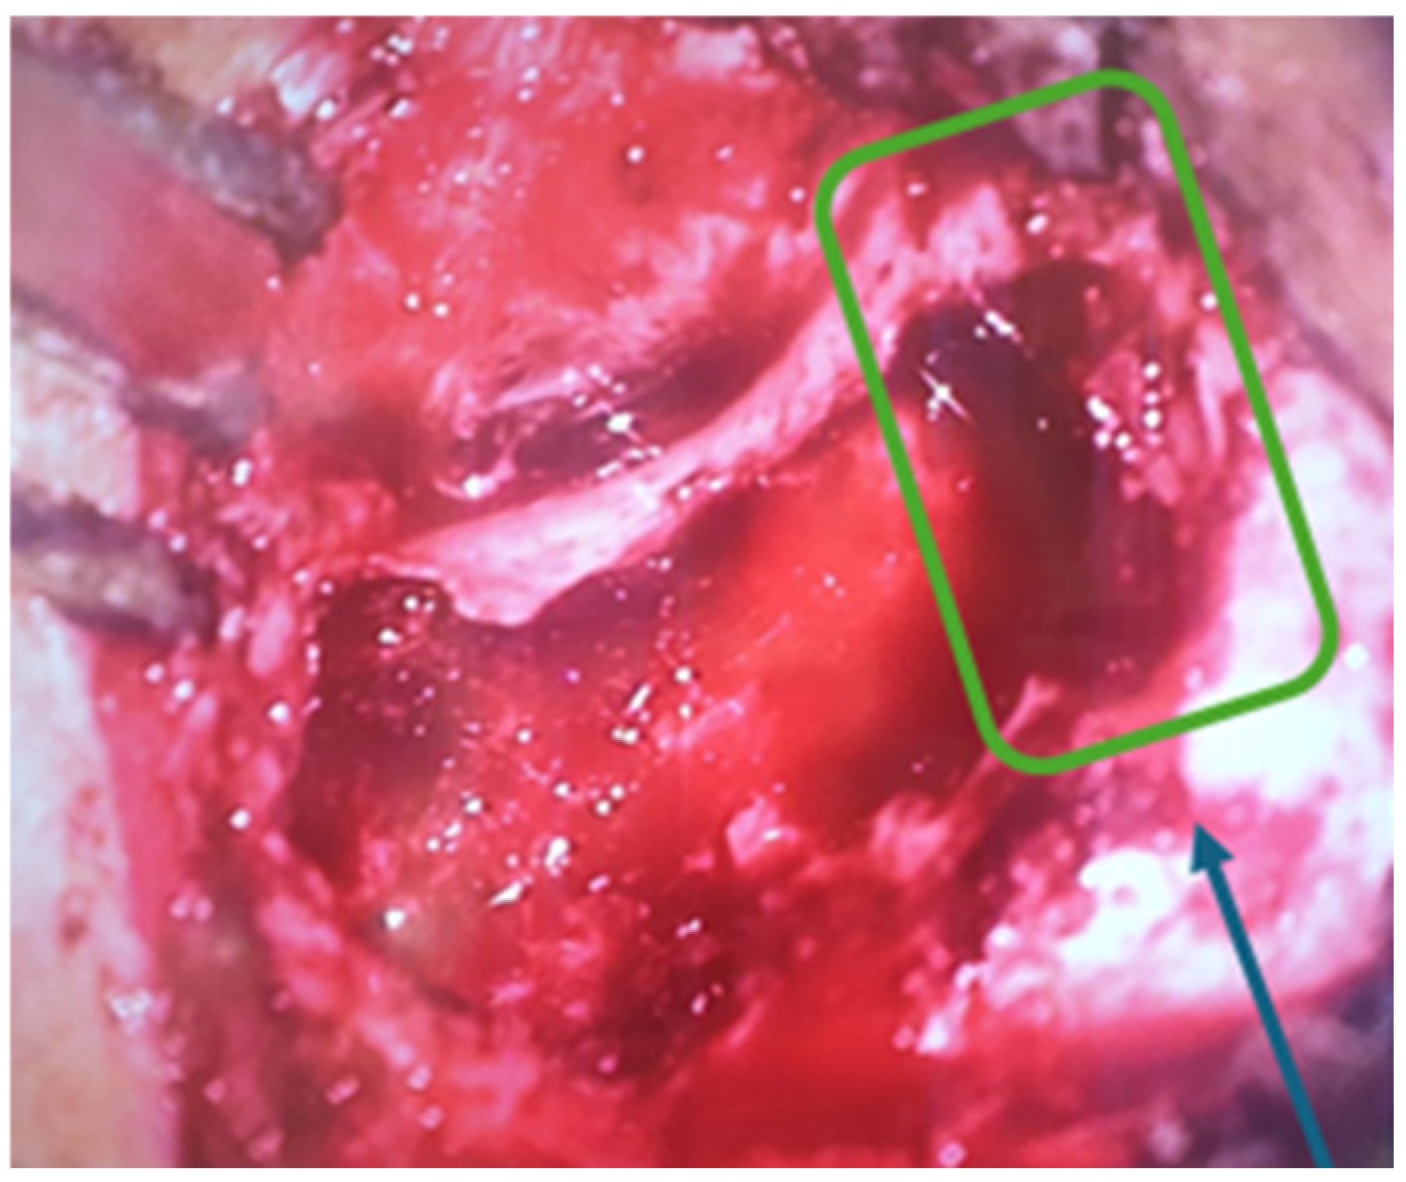

A surgical intervention was performed—radical trepanation. It started with retroauricular incision and mastoid bone exposure. As we started drilling of the mastoid bone, there was a destruction of the normal mastoid bone structure by a soft tissue mass, which was filling the entire mastoid beneath the cortex. The aditus was also blocked by that soft tissue. Following the destruction in a cranial direction, there was a 3 cm zone of exposed durra matter (Figure 4). After removing of the posterior wall of the external auditory channel, there was a large defect (Figure 5), through which the soft tissue was spreading from the mastoid to the external auditory channel. Step by step a classical radical trepanation cavity was formed. Tympanic membrane and ossicular chain remnants were visualized and removed. During the inspection of the tympanic cavity, a small tumour mass, which causes profuse bleeding if touched, was found in the area of the Eustachian tube hole. Intraoperative frozen section biopsies of the other soft tissue masses were all negative for malignant tumour cells and because of that, a decision for postoperative MRI around 30 days after the surgery was taken to clarify the surgical finding.

Figure 4. Exposed dura mater.

Figure 5. Dehiscence of the external auditory canal wall.